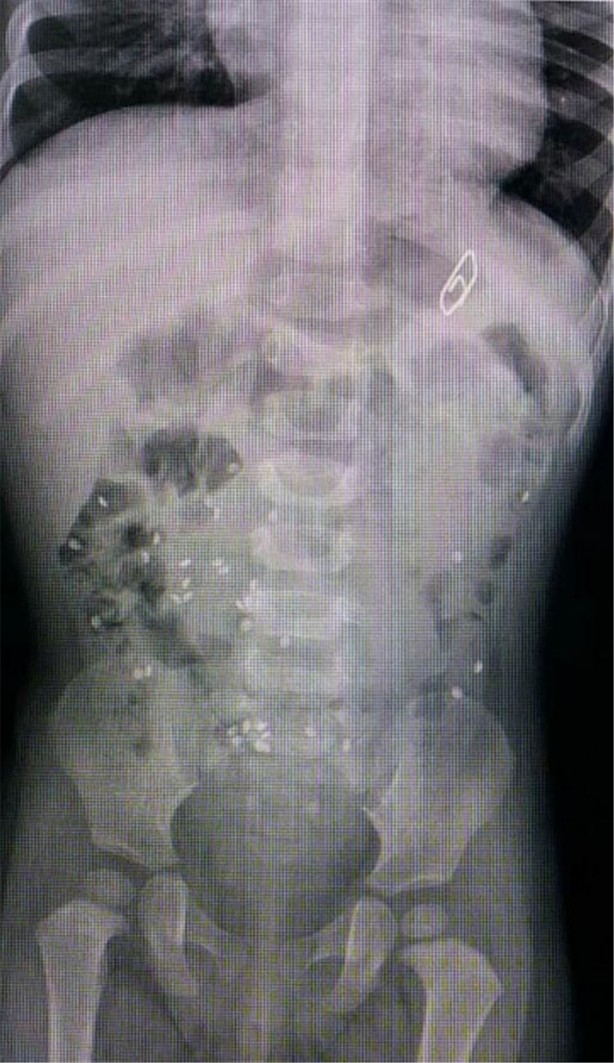

İzmir Tepecik Eğitim ve Araştırma Hastanesi Çocuk Gastroenteroloji Bölümü'nün, yabancı cisim yutan çocukların nefes ve borusu ile midelerinden çıkarttığı, anahtarlık, madeni para, saat pili, ataç, çengelli iğne ve çivi gibi objeler görenleri hayrete düşürdü.

Bu objelerden en tehlikelisinin piller olduğuna dikkat çeken Doç.Dr. Maşallah Baran, "Piller kimyasal mekanizmayla mukozayı yakıyor, özellikle yemek borusu çok duyarlı pillere, hele ki yeni takılmış bir pilse saatler içinde şahit olduğum bir kaç vaka var, yemek borusunu kömür haline getirebiliyor" dedi.